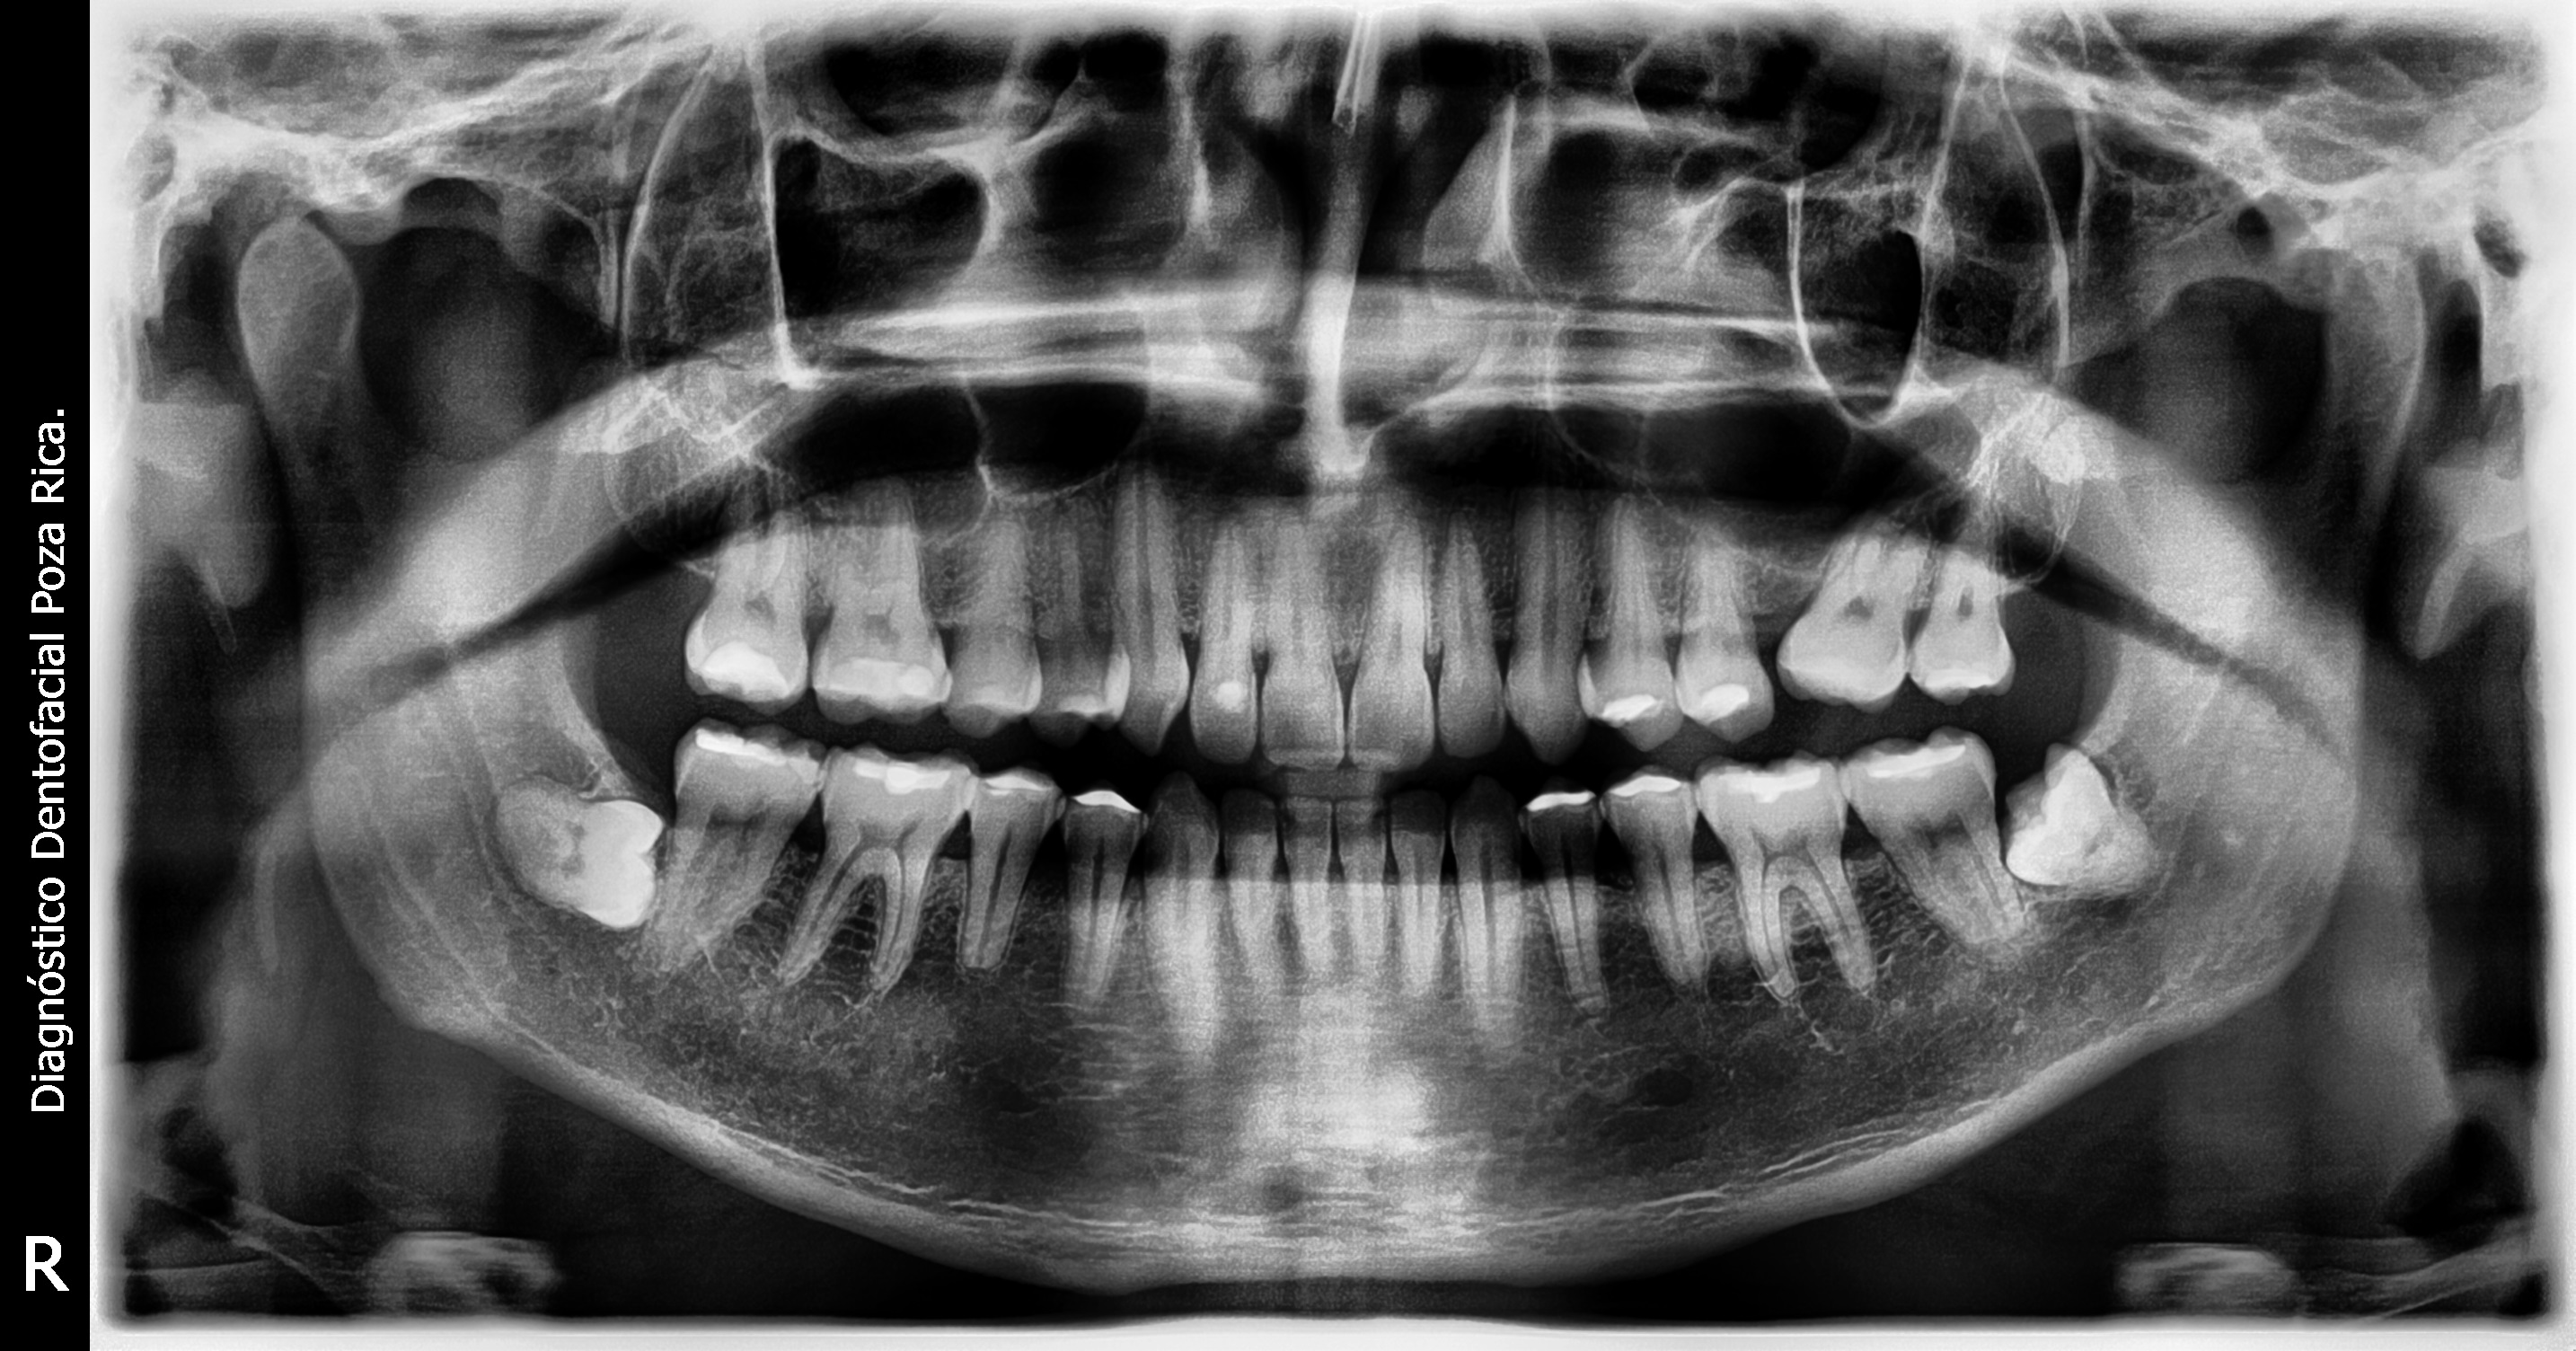

La radiografía digital debido a sus múltiples ventajas es la mejor opción para usted en el diagnóstico odontológico. Son muchas las ventajas que ofrece la radiografía digital, entre las cuales están las siguientes:

- Mayor información para sus pacientes: usted podrá mostrar a sus pacientes las radiografías obtenidas y así logrará darles un mejor entendimiento de los diagnósticos.

- Mayor calidad y rapidez de las imágenes radiográficas: en una radiografía convencional, el ojo humano detecta de 28 a 32 tonos de gris; con la radiografía digital se pueden detectar hasta 256 tonos.

- Facilita el diagnóstico clínico: mediante el uso de un potente software de tratamiento de imágenes, se pueden tratar las mismas, ampliándolas, acentuando brillos y contrastes, resaltándolas mediante efectos 3D, etc.